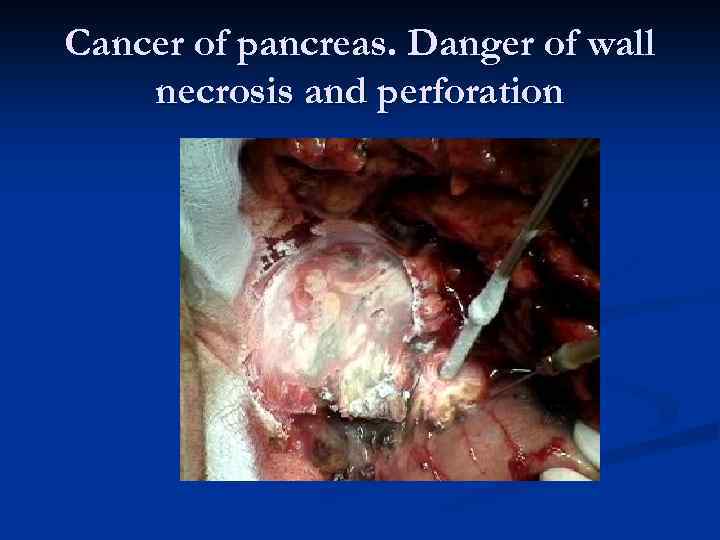

Cancer of pancreas. Danger of wall necrosis and perforation

Cancer of pancreas. Danger of wall necrosis and perforation